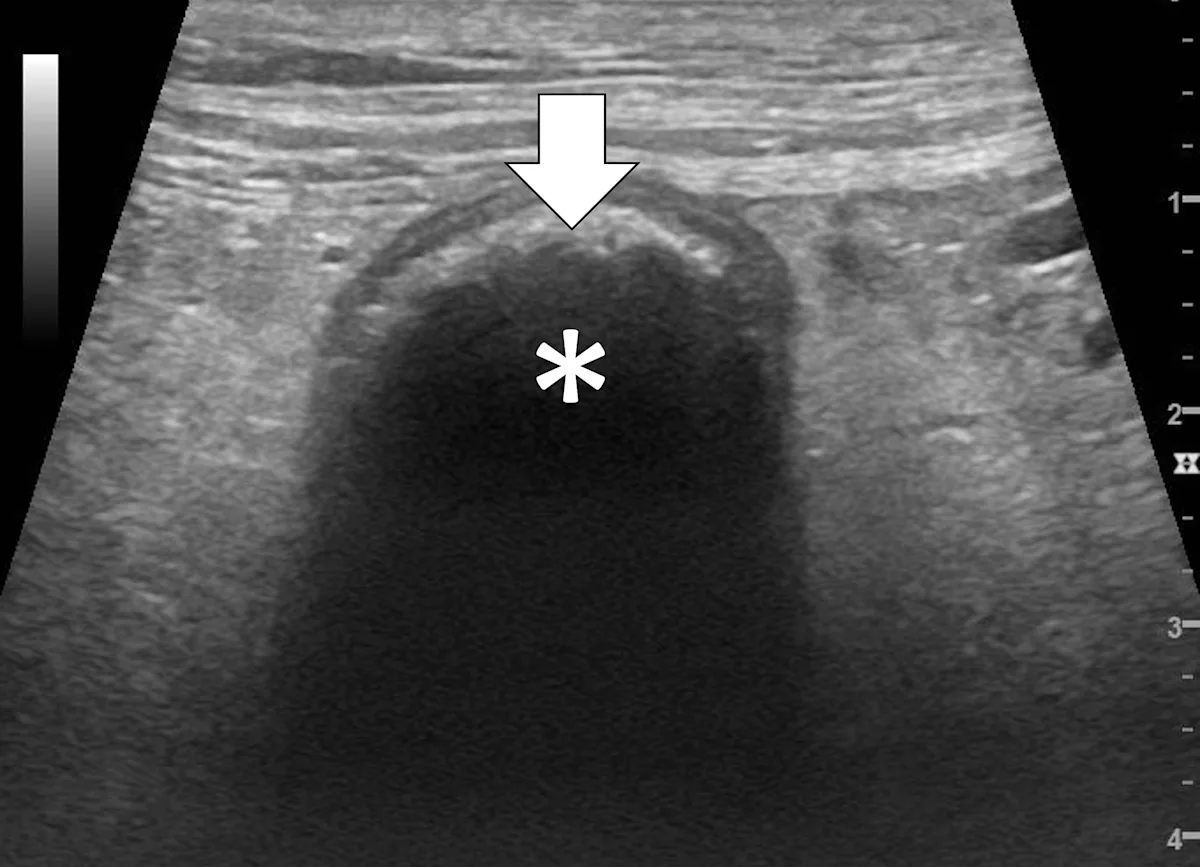

Pyloric outflow obstructions occur when a foreign body lodges in the pyloric outflow tract or the proximal duodenum and can cause variable gastric distention depending on the length of time the obstruction has occurred and whether the patient has recently vomited (Figure 2). Diagnosis of this type of obstruction via ultrasonography requires identification of an intraluminal structure that is causing gastric or proximal duodenal dilation orad to the foreign body.9-12 Foreign bodies are easier to see when surrounded by fluid. Although exceptions are possible, acute complete obstructions typically cause mild to moderate gas dilation, and chronic partial obstructions can cause more moderate to severe dilation, predominately with fluid.

FIGURE 2A

Abdominal ultrasound of a 3-year-old neutered male crossbreed dog with a surgically confirmed mechanical pyloric outflow obstruction. A homogeneously hypoechoic potato (asterisk) is present in the pylorus and completely visible due to its similar acoustic impedance as the surrounding soft tissues. There is transition from gas in the gastric lumen to the foreign body (white arrow). The remainder of the gastric lumen (pound sign) is not visible due to gas (black arrows) causing a hyperechoic surface with reverberation artifact.

Only the gastric wall located in the near field is visible if the stomach is filled with gas. The stomach may need to be evaluated from multiple angles, including subxiphoid, subchondral, right intercostal, and left intercostal. The pylorus shifts craniodorsally and is more difficult to see when the stomach enlarges and the patient is in dorsal recumbency. In these situations, the right intercostal approach can make finding the pylorus and proximal duodenum easier. Evaluating the stomach with the patient in different positions (eg, dorsal recumbency, lateral recumbency, standing) changes the distribution of fluid and gas and may aid in foreign body detection. Gas within the lumen of the stomach masks intraluminal structures; therefore, ultrasonography cannot rule out a gastric foreign body in a gas-dilated stomach.